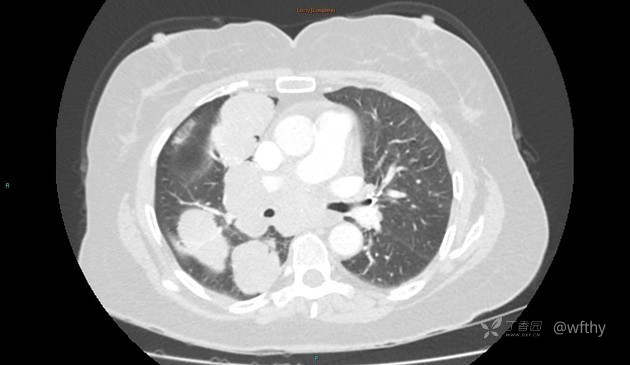

病例女65,头部肿块